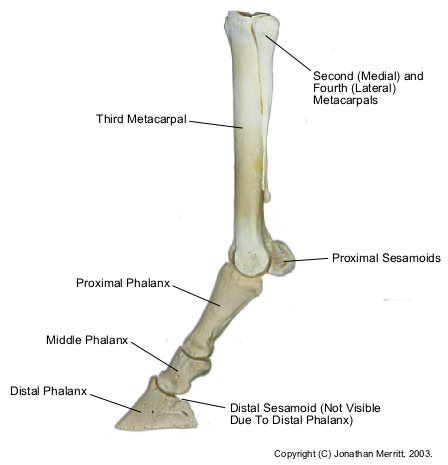

The proximal sesamoid bones in the horse are two small bones sitting at the base of the cannon bone in back of the fetlock joint. They are critical components of the suspensory apparatus that supports the horse's distal limb. The suspensory ligament originates from the bottom of the carpus (knee) or tarsus (hock) and runs down the back of the cannon bone, attaching to the top of the proximal sesamoid bones. The distal sesamoidean ligaments originate from the bottom of the proximal sesamoid bones and run down the back of the pastern, attaching at the back of the long and short pastern bones. The suspensory ligament, proximal sesamoid bones, and distal sesamoidean ligaments make up the suspensory apparatus of the fetlock joint and work together to prevent overextension of this joint when the limb is fully weight-bearing. Because the proximal sesamoid bones are integral in the suspensory apparatus of the distal limb, they cannot be successfully removed.

Sesamoiditis refers to pain associated with the proximal sesamoid bones. It often results from inflammation at the interface of the suspensory ligament and distal sesamoidean ligaments with the sesamoid bones. It is caused by unusual strain to the fetlock joint. It is most often seen in racehorses and jumpers, but it can be seen in any breed or discipline of horse.

A definitive diagnosis of sesamoiditis is made by taking radiographs (X rays) of the fetlock joint and sesamoid bones. Radiographic changes include increased size and number of vascular channels within the bone, calcification (hardening) of soft tissue structures surrounding the bone, proliferative bony production on the sesamoid bones, and avulsion (separating) fractures at the attachments of the suspensory ligament and distal sesamoidean ligaments to the sesamoid bones. If sesamoiditis is diagnosed based on radiographs, it is important to also ultrasound the suspensory ligament and